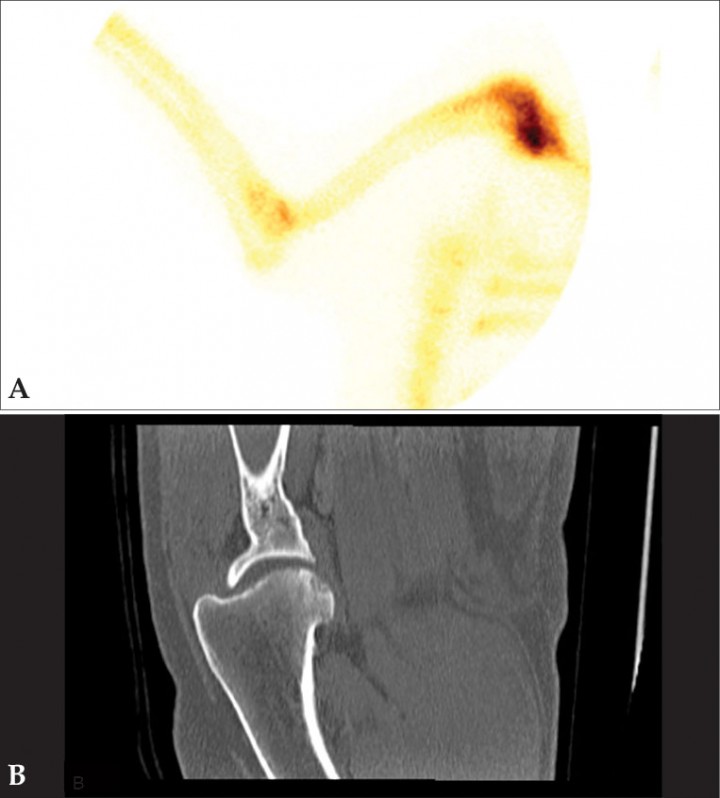

Ocasionalmente, el examen clínico puede no ser concluyente en la localización de la cojera debido a que el paciente presente una gran tolerancia al dolor, ausencia de palpación de anomalías morfológicas o no permita el examen por estrés, agresividad o hiperestesia.[ Schwarz T, Johnson VS, Voute L, Sullivan M. Bone scintigraphy in the investigation of occult lameness in the dog. J Small Anim Pract. 2004; 45(5):232-237. [PubMed] , Samoy Y, Van Ryssen B, Van Caelenberg A et al. Single-phase bone scintigraphy in dogs with obscure lameness. J Small Anim Pract. 2008; 49(9):444-450. [PubMed] ] La radiología puede así mismo no ser concluyente, ya que los cambios radiológicos pueden retrasarse en su aparición o no reflejar la causa de la cojera. La gammagrafía es una técnica muy sensible para detectar cambios tempranos en la remodelación ósea y/o verdadera patología y para evaluar la actividad de la lesión.[ Schwarz T, Johnson VS, Voute L, Sullivan M. Bone scintigraphy in the investigation of occult lameness in the dog. J Small Anim Pract. 2004; 45(5):232-237. [PubMed] , Samoy Y, Van Ryssen B, Van Caelenberg A et al. Single-phase bone scintigraphy in dogs with obscure lameness. J Small Anim Pract. 2008; 49(9):444-450. [PubMed] ] Por ejemplo, en el diagnóstico diferencial de cojeras del miembro anterior permite determinar si la patología tiene su origen en el codo (fragmentación del proceso coronoides medial) o en el hombro (lesiones del sistema extensor o contracturas del músculo infraespinoso/supraespinoso). Al localizar anatómicamente la lesión, es posible restringir a la zona afectada los estudios de tomografía computarizada (TC) o artroscopia (Figs. 11-13).[ Samoy Y, Van Ryssen B, Van Caelenberg A et al. Single-phase bone scintigraphy in dogs with obscure lameness. J Small Anim Pract. 2008; 49(9):444-450. [PubMed] , Van Bruggen LW, Hazewinkel HA, Wolschrijn CF, Voorhout G, Pollak YW, Barthez PY. Bone scintigraphy for the diagnosis of an abnormal medial coronoid process in dogs. Vet Radiol Ultrasound. 2010; 51(3):344-348. [PubMed] , Debruyn K, Peremans K, Vandermeulen E, Van Ryssen B, Saunders JH. Evaluation of semi-quantitative bone scintigraphy in canine elbows. Vet J. 2013; 196(3):424-430. [PubMed] ]

<p>Estudio de un paciente canino con dolor inespecífico en extremidad anterior izquierda. (<strong>A</strong>) Gammagrafía ósea, adquisición en fase ósea 2 horas después de la administración de <sup>99m</sup>Tc-HDP, proyección ventral de las extremidades anteriores en las que se observa un foco con aumento de captación del radioisótopo en la región de la articulación del codo izquierdo, principalmente en la porción distal de la misma. La imagen es compatible con patología del proceso coronoides medial. (<strong>B</strong>) TC del codo izquierdo del mismo paciente, plano transversal en algoritmo hueso en el que se observa un área hipoatenuante en el coronoides medial sin línea de fractura evidente, compatible con condromalacia y enfermedad de coronoides medial sin presencia de fragmentos. La gammagrafía permitió en este caso localizar la articulación con patología (codo) que es la que se examinó con la TC.</p>

Estudio de un paciente canino con dolor inespecífico en extremidad anterior izquierda. (A) Gammagrafía ósea, adquisición en fase ósea 2 horas después de la administración de 99mTc-HDP, proyección ventral de las extremidades anteriores en las que se observa un foco con aumento de captación del radioisótopo en la región de la articulación del codo izquierdo, principalmente en la porción distal de la misma. La imagen es compatible con patología del proceso coronoides medial. (B) TC del codo izquierdo del mismo paciente, plano transversal en algoritmo hueso en el que se observa un área hipoatenuante en el coronoides medial sin línea de fractura evidente, compatible con condromalacia y enfermedad de coronoides medial sin presencia de fragmentos. La gammagrafía permitió en este caso localizar la articulación con patología (codo) que es la que se examinó con la TC.

<p>Estudio por imagen de un perro con cojera de la extremidad anterior izquierda. (<strong>A</strong>) Gammagrafía en fase ósea en la que se aprecia aumento de captación de <sup>99m</sup>Tc-HDP en la articulación escapulohumeral. (<strong>B</strong>) Reconstrucción sagital de TC de hombro izquierdo en algoritmo hueso con pequeños defectos subcondrales en la superficie caudal de la cabeza humeral compatible con osteocondrosis (TC cortesía de ARS Veterinaria). La gammagrafía permitió en este perro de raza grande (montaña del Pirineo) localizar la articulación que presentaba patología para realizar la TC solo de la región anatómica afectada.</p>

Estudio por imagen de un perro con cojera de la extremidad anterior izquierda. (A) Gammagrafía en fase ósea en la que se aprecia aumento de captación de 99mTc-HDP en la articulación escapulohumeral. (B) Reconstrucción sagital de TC de hombro izquierdo en algoritmo hueso con pequeños defectos subcondrales en la superficie caudal de la cabeza humeral compatible con osteocondrosis (TC cortesía de ARS Veterinaria). La gammagrafía permitió en este perro de raza grande (montaña del Pirineo) localizar la articulación que presentaba patología para realizar la TC solo de la región anatómica afectada.